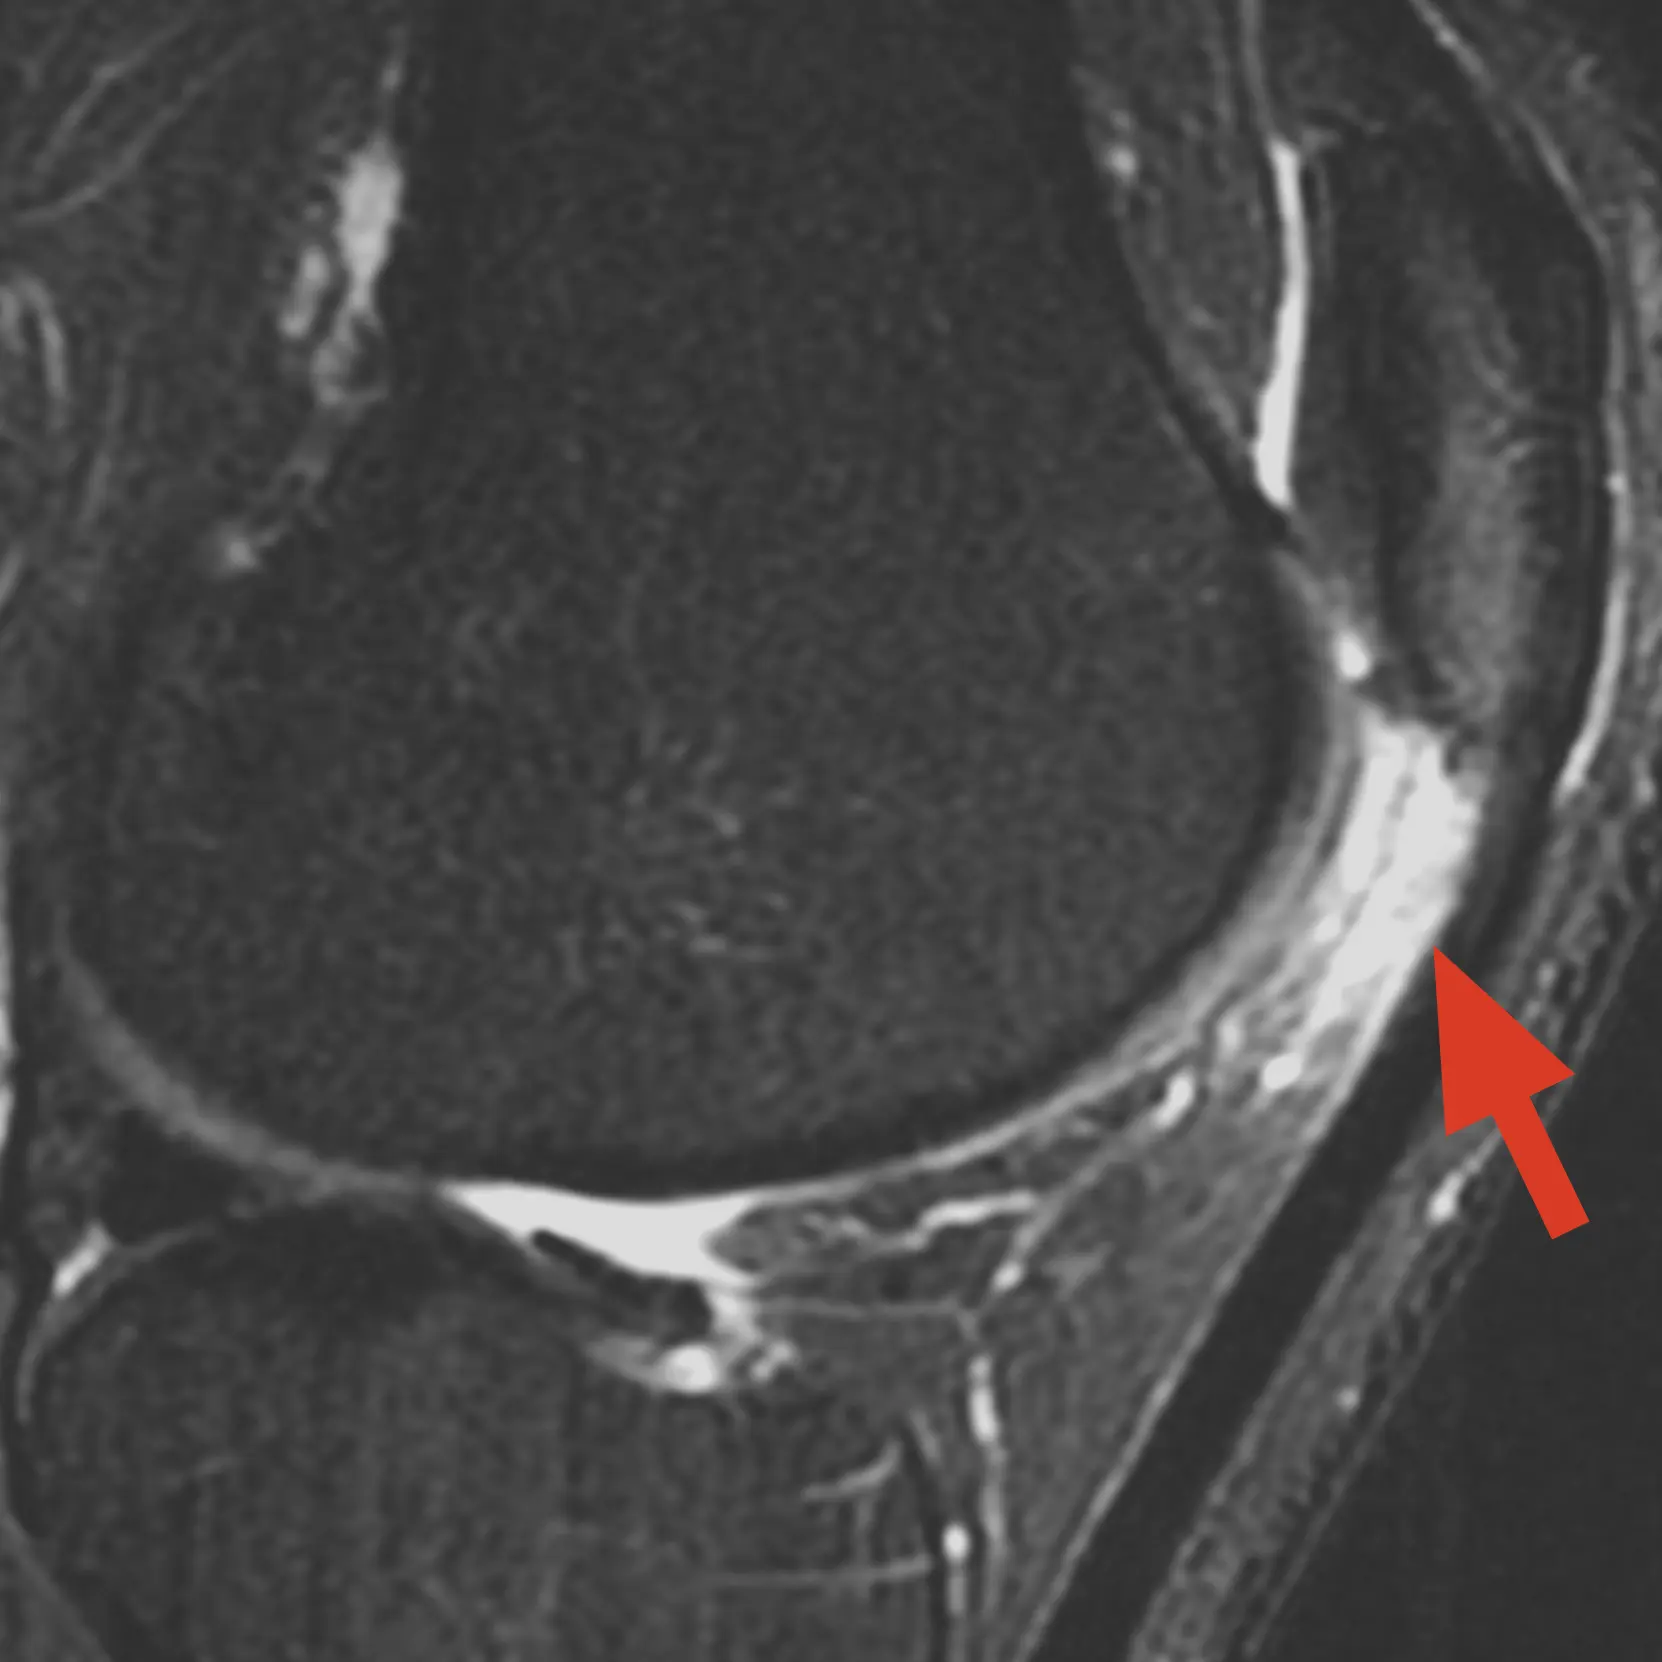

MRI of knee fat pad impingement (Hoffa's Syndrome) with arrow pointing to the inflammation below the patella

MRI showing the location of Hoffa's Fat Pad and typical impingement zone.

• MRI scan: can show fat pad inflammation, scarring, oedema, and associated issues such as cartilage damage or patellofemoral problems